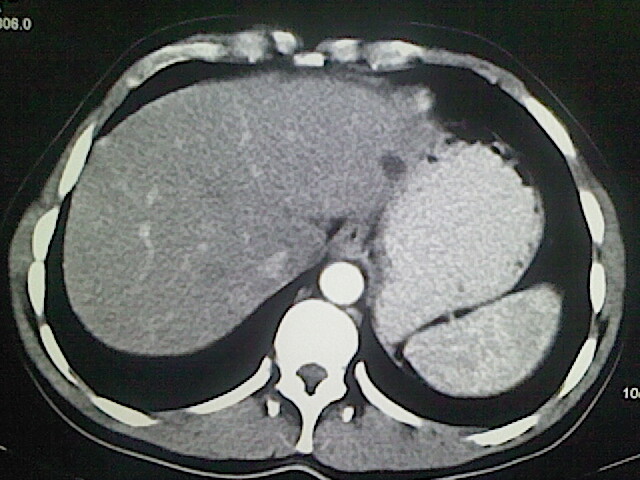

以下是引用卜一在2009-3-14 9:49:00的发言:[br]胆囊萎缩,胆囊壁不规则增厚,内部结构模糊,增强明显强化。另:肝左叶外侧段肝囊肿。支持:慢性胆囊炎!高度可疑:胆囊癌!

以下是引用余辉在2009-3-14 8:48:00的发言:[br]1)慢性胆囊炎。2)肝左叶外侧段肝囊肿。3)脂肪肝。[br]支持,胆囊萎缩,密度增高,不知b超具体有何提示,钙胆汁?结石?

以下是引用jiangjing在2009-3-14 10:18:00的发言:[br]1)慢性胆囊炎。2)肝左叶外侧段肝囊肿。3)脂肪肝。4.】建议行肝功能检查